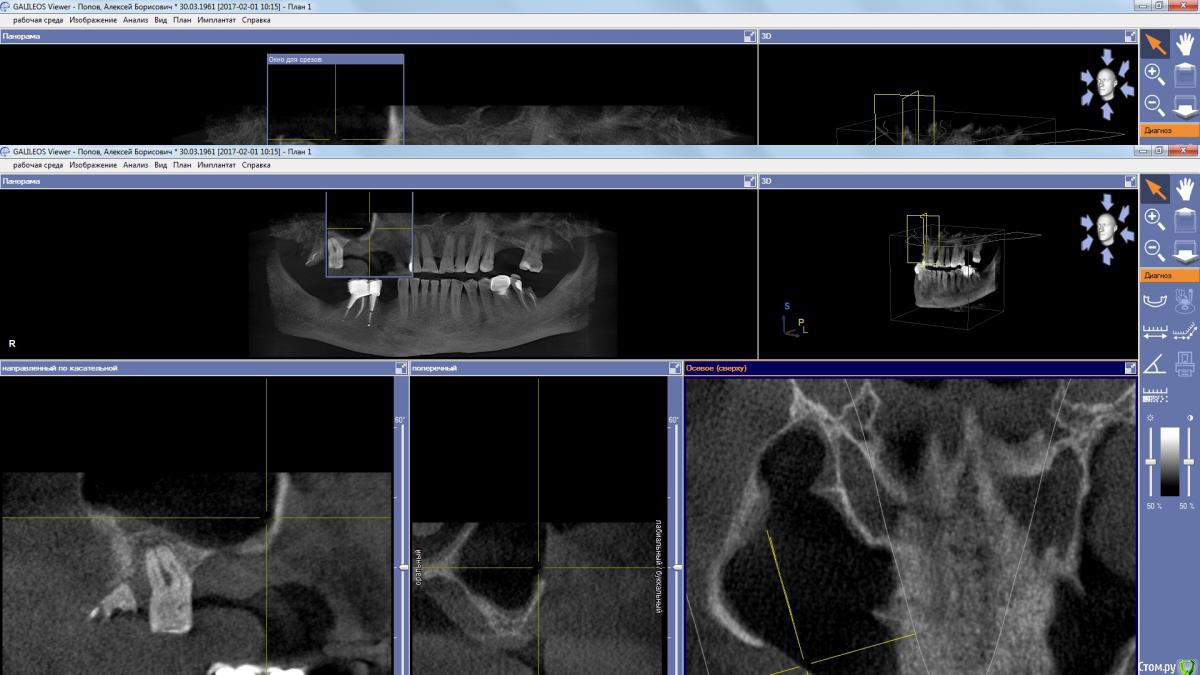

kamranchick Опубликовано 25 декабря, 2017 Автор Поделиться Опубликовано 25 декабря, 2017 (изменено) Чтобы не создавать новую тему...Пациента отправил на санацию ВЧП к лору, но вот такое дал заключение и сказал можно резать, ваше мнение? Изменено 25 декабря, 2017 пользователем kamranchick Ссылка на комментарий

red_butler Опубликовано 25 декабря, 2017 Поделиться Опубликовано 25 декабря, 2017 Другие ЛОРы по близости есть? Я бы до санации пазухи не лез. Ссылка на комментарий

Bier Опубликовано 26 декабря, 2017 Поделиться Опубликовано 26 декабря, 2017 ретенционку удали сам, через верхний доступ, этажем ниже делай синуслифт, если боишься, то в 2 этапа. Ссылка на комментарий

Irouil Опубликовано 27 декабря, 2017 Поделиться Опубликовано 27 декабря, 2017 Имхо не ретенционная, соустье вероятно перекрыто. Ссылка на комментарий